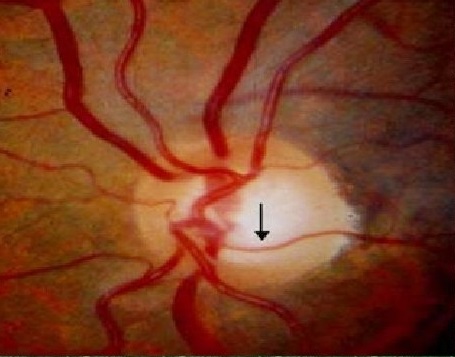

<함몰이 없는 국소창백, Overpass cupping>

Overpass 라는 것은 육교, 다리 라는 단어입니다.

Overpass cupping 이라는 것은 문자그대로 혈관이 시신경유두 위를 육교 다리처럼 놓여있다는 의미입니다.

이는 실제 함몰된 시신경유두 위에 육교처럼 있다는 말이 아니라,

마치 함몰된 것처럼 보이는 창백한 시신경유두 위에 육교처럼 놓여있다는 것을 의미하는 용어입니다.

정상적인 상태에서는 시신경유두의 함몰이나 창백이 없는상태로,

정상적인 시신경유두의 혈관이 시신경유두 표면에 놓여있는 상태에 있습니다.

녹내장이 발생하게되면서, 점점 시신경유두에 압력이 가해지면, 아직함몰을 발생하지 않았지만,

국소적인 허혈 상태로 인해서, 혈관아래에 있는 망막조직이 허혈로 인해 창백해지게 됩니다.

즉, 아직 함몰이 발생하지는 않았지만, 국소적인 허혈로 인한 창백으로 인해,

마치 시신경 유두의 혈관이 투명한 창백부위를 육교나 다리처럼 이어주게되는 식으로 보이게되는 상태를, Overpass cupping 이라고 합니다

Overpass cupping 은

망막혈관이 위치하는 망막표층과 사상판조직(lamina cribrosa) 사이의 조직이 투명해짐으로써, 마치 유두함몰처럼 보이지만 실제 함몰은 되지 않아 혈관 주행의 변화는 없는 상태를 의미합니다.